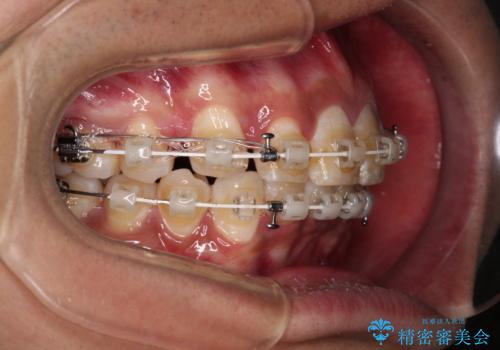

深い咬み合わせと前歯のデコボコ ワイヤー装置での抜歯矯正

- 深い咬み合わせと前歯のデコボコを改善したいとのことで来院された患者様です。

口元の突出感はないものの、上顎前歯のデコボコが著しく、右側の咬み合わせがずれていたため、上顎右側第一小臼歯1本を抜歯することとしました。

咬合力が非常に強く、抜歯したスペースがなかなか閉じないであろうことは予想できましたが、思っていた以上に期間がかかりました。

前歯のすり減りも著しかったため、仕上げの位置の調整にも期間を要しました。